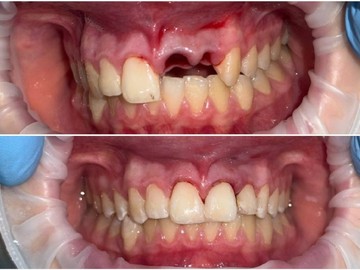

Атравматичное удаление зубов – наиболее безболезненная и щадящая процедура, которая практически не травмирует десну и костную ткань.

Зуб извлекается частями, что позволяет не травмировать окружающие ткани.